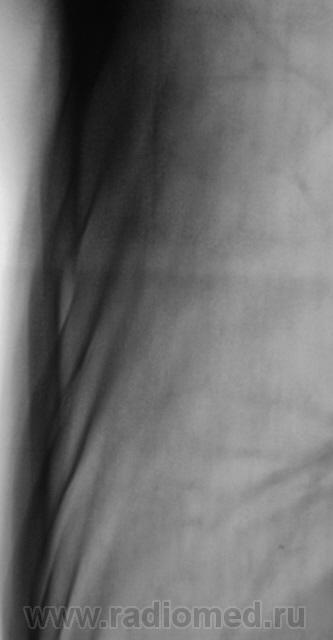

В связи с появившейся осиплостью голоса пациенту была проведена томография гортани.

1 - п/е первого контроля (снимки 4-9) - как отразили динамику (описание/заключение)?

- изменения в левом лёгком (Написал бы - гиповентиляция н/доли?) не нашли отражения на Т-граммах (частично - 9 срез) : рекомендовал бы ФБС!

2 - прицельные Т-граммы на втором контроле : думаете патологические переломы (или уверены), травматический анамнез?

3 - На Т-графии гортани - изменения в правой стенке : ПОДТВЕРЖДЕНЫ лорами (биопсия?)?

С учетом срезы 11 см (снижение прозрачности легочной  ткани в медиальных отделах верхушечных сегментов), нами динамика была оценена, как "отрицательная.

ФБС была сделана в областном учреждении.

Томография гортани была также произведена в "области". ЛОРами был взят материал для биопсии.